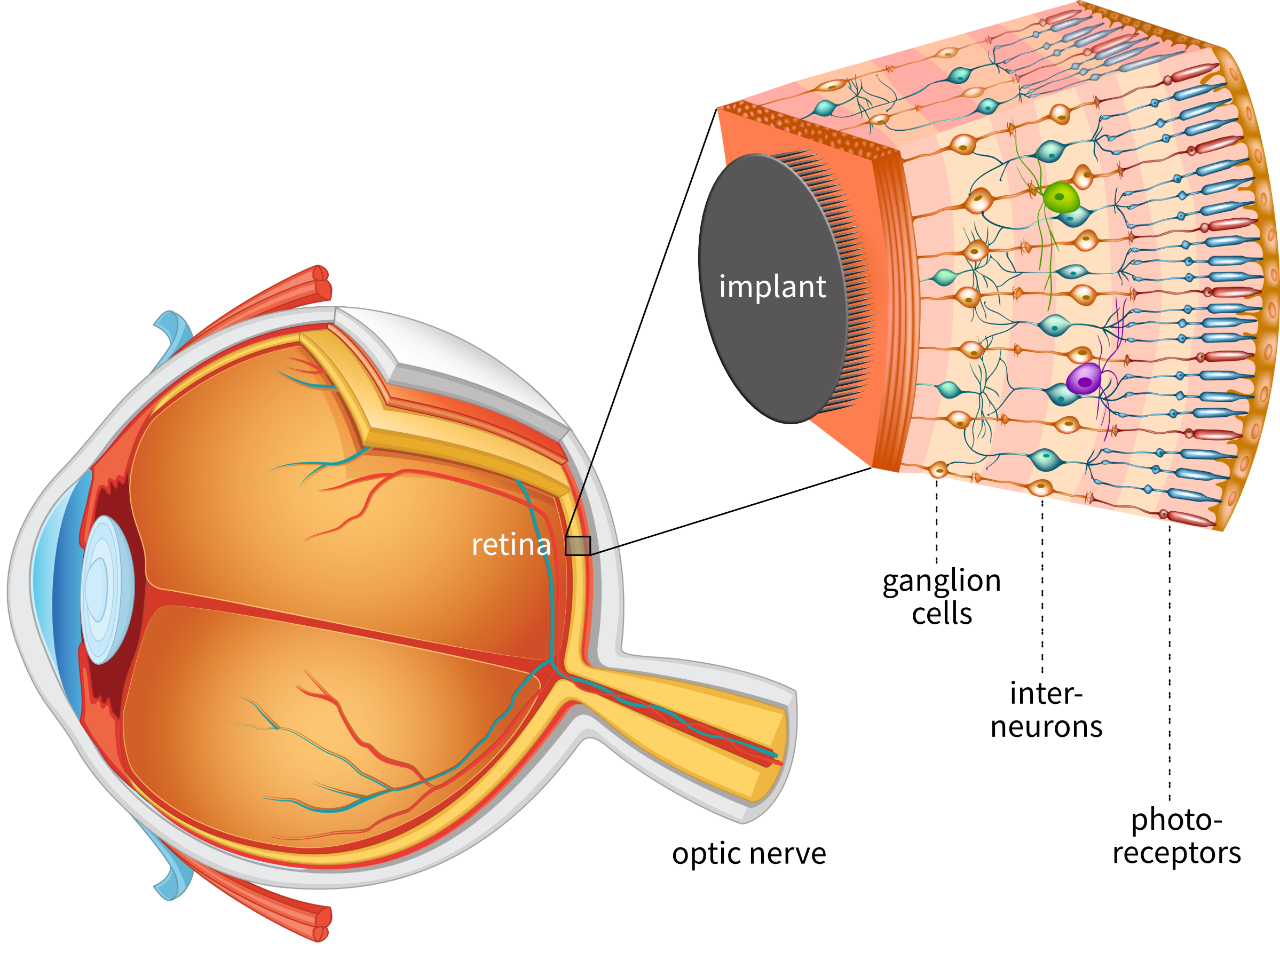

Изображения и анатомия сетчатки глаза

Раздел: Визуальный дайджест